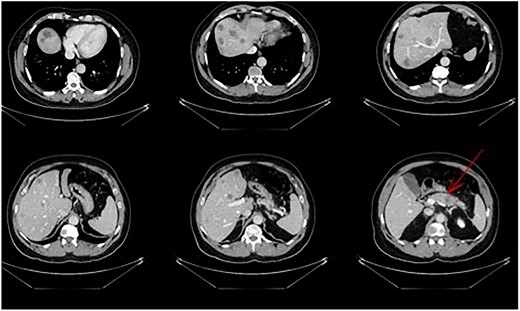

The postoperative course was uneventful and the patient was discharged after 7 days, followed by TACE of the right lobe 3 weeks after surgery. After 6 weeks, the patient received his first dose of the systematic chemotherapy with FOLFIRINOX. A follow-up CT scan confirmed that all remaining LMs in the right lobe had significantly decreased in size or vanished (Fig. 2). Tumor markers (CA19-9 and CEA) decreased continuously to normal levels (Figs. 3 and 4).

Status post-multimodal therapy with significant lesional downsizing or complete vanishing of cancerous lesions.